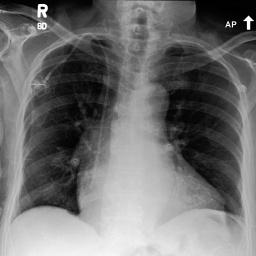

Image Reconstruction. Table 1 shows that the co-training scheme outperforms the \mathcal{E}-training approach in reconstruction accuracy, as indicated by higher PSNR and IW_SSIM scores, highlighting the benefits of joint optimization for enhancing reconstruction quality. The results are further validated by the visual comparison in Fig. 2, where the co-training scheme recovers input images with finer details and higher fidelity. In contrast, the \mathcal{E}-training scheme exhibits noticeable discrepancies when compared to the original images.

Refer to caption

XRX_{R}

Co-training

\mathcal{E}-training

Fig. 2: Reconstruction results. The first row displays the real images XRX_{R}. The last two rows show the reconstructed images X^R\hat{X}_{R} produced by the proposed co-training scheme and the \mathcal{E}-training scheme, respectively.